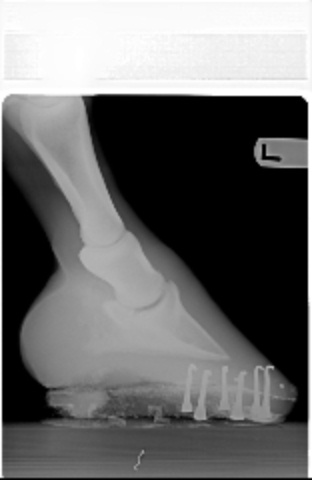

Posted on Tuesday, Apr 26, 2005 - 11:25 pm: This vet seems to feel that the farrier's work is to blame...however, he also respects my farrier and thinks I made a good choice.Here are the xrays from the farrier series.

Posted on Wednesday, Apr 27, 2005 - 7:24 pm: I was just thinking his toes looked long and I was impressed by the number of nails plus clips to hold the shoes on. If his angles are different than they normally are, or if they were changed very much in one shoeing, it could be enough to make the horse lame, at least for a while. I don't feel qualified to comment on anything else, but think you should wait for Dr. O's comments. |

Posted on Thursday, Apr 28, 2005 - 8:22 am: Concerning your vets statements no I do not think the injections were diagnostic one way or the other and agree with Sara, if at all possible I would like to see the toe squared off more.DrO |

Posted on Wednesday, Jul 20, 2005 - 12:49 am: Dear Aileen,In viewing your xrays, I am wondering if the nail closest to the apex of the (I don't know the exact name) bone, in the right front is supposed to be that close to that bone. Do you know Dr.O ? The hind looks too short. The front right has a longer toe and higher heel. The left has a lower heal and a more rounded toe. It may be the photo but they look uneven to me. I have been through 3 shoers in six years. All with impeccable resumes. Go figure. There is a Farrier College/Hoof Hospital in Salinas, California. I have heard people trailer in from different states all the time just to get a horse shod correctly once. Then a good farrier can follow the balance of all 4 hooves. Brave is gorgeous. I do agree with the others, he could lose a little in the middle. Especially during this tremendous summer heat wave. All of the top trainers keep their horses quite fit. Although photos do add weight to any image.  Good Luck!! WTG |

Posted on Wednesday, Jul 20, 2005 - 7:36 am: WTG since the radiographs are 2 dimensional and we only have lateral views you cannot evaluate the nails positions with respect to the bone. For instance the nail could be tapped to the outside of the foot and would have the same appearance.Ailleen the angles, distance, and low light make evaluation difficult. Better would be to maintain the distance but to telephoto in just a bit to the point where you get distal cannon, fetlock and hook. Flash or outside with the sun behind you will improve the lighting. Also the closer the camera is to the ground, to avoid foreshortening, the better. DrO |